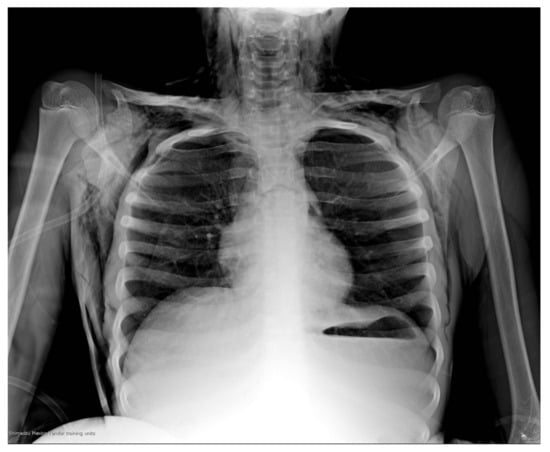

The arterial gases showed decompensated respiratory acidosis with hypercapnia. The chest X-ray (Figure 1) showed no evidence of an FB; however, it presented frank hyperinflation data, a small pneumothorax located in the upper part of the left hemithorax, as well as subcutaneous emphysema in the neck and chest. The rest of the laboratory studies did not present relevant data for the case.

Figure 1. Plain chest radiograph in anteroposterior projection on admission of patient to the ED. A small pneumothorax can be observed in the upper right part of the left hemithorax of approximately 20%, as well as signs of pulmonary hyperinflation, with horizontalization of the costal arches; subcutaneous emphysema can also be observed in the neck and both hemithorax. Unable to visualize the FB.

On suspicion of the aspiration of an FB, chest radiography is suggested, with anteroposterior and lateral vertical projections; a lateral soft tissue neck radiograph is also suggested [1,6]. The most frequent findings are the visualization of the FB, although it is considered that of the FBs aspirated only 8.2–24% are radiopaque, lobar or segmental radiolucency, areas of atelectasis, and inflammatory consolidation of the pulmonary parenchyma unilateral or bilateral hyperinflation. The presence of pneumothorax, subcutaneous emphysema, and pneumomediastinum are less frequent [1,12,14]. Although it is also common to routinely obtain a simple lateral decubitus chest X-ray, some studies confer it a limited role in diagnosis, with only a sensitivity of 27% and a specificity of 67%. On the other hand, although computed tomography is superior to a chest X-ray (especially in the case of radiopaque foreign bodies), with a sensitivity of 100% and a specificity of 66.7%, it has some limitations, such as: radiation exposure and the restriction of movement required for high-quality scans, which is often not feasible in people with respiratory distress [2]. In the presence of a negative chest X-ray, and high suspicion of FB aspiration, it is necessary to perform bronchoscopy [6,15].